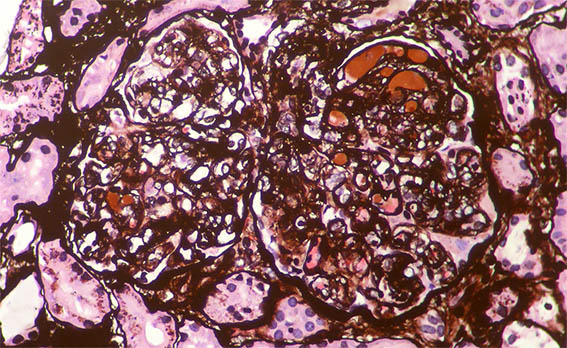

Look at the images of the kidney biopsy:

Figure 1. H&E, X400. Note the lobulation and hypercellularity, mainly mesangial in this image.

Figure 2. H&E, X400. In this glomerulus there is endocapillary hypercellularity, in addition, subendothelial deposits in the lower right corner.